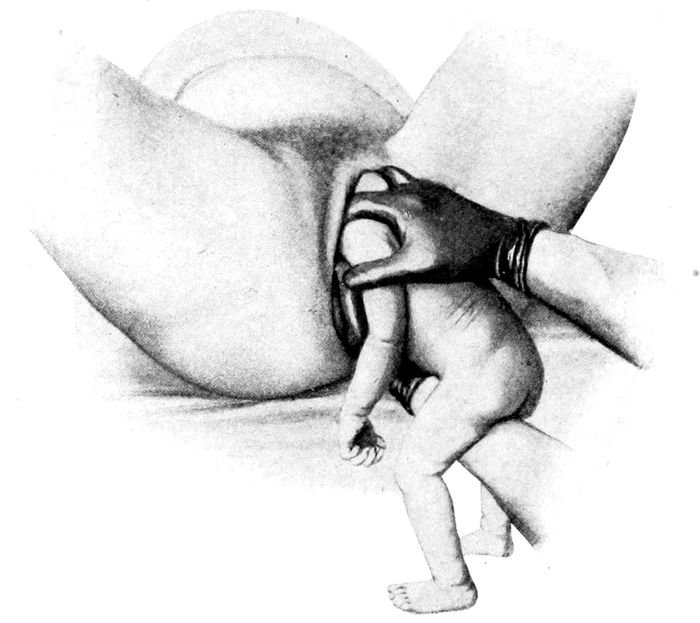

Extraction of the breech |

170 |

| |

| 64. |

Breech delivery. Extraction of the trunk |

171 |

| |

| 65. |

Breech delivery. Delivering the shoulder |

172 |

| |

| 66. |

The delivery of the after-coming head by the Smellie-Veit maneuver |

172 |